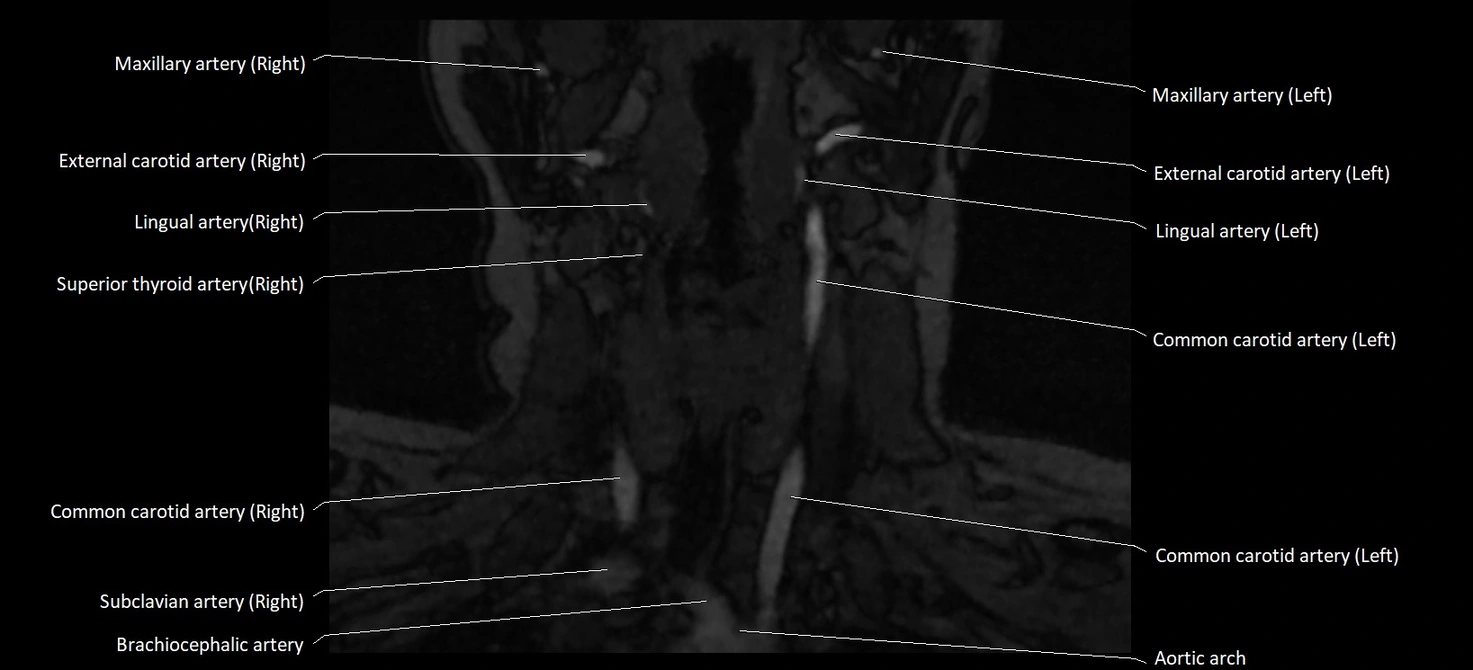

MRI images

CT image